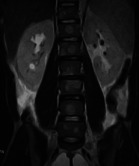

There are a few reported cases of bone metastasis from adenocarcinoma of the appendix and there is none from Africa. We report this rare case of a 30-year-old man who presented with low back pain following a trivial fall and who subsequently developed generalized peritonitis for which he underwent laparotomy. The histology of the appendix and the mesentery confirmed adenocarcinoma of the appendix with metastasis to the mesenteric lymph nodes while an MRI scan confirmed spine metastasis. Carcinoma of the appendix, should, therefore, be considered as a differential diagnosis in spine metastasis of unknown origin especially with coexisting abdominal symptoms.

Abstract Image